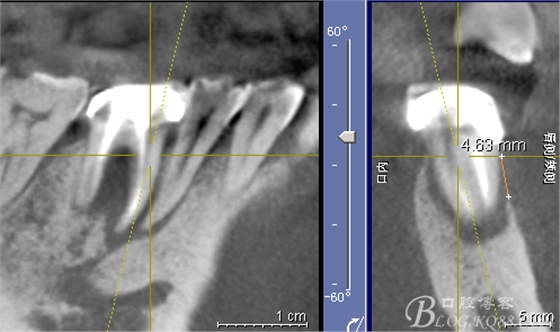

CT可見(jiàn)根管內(nèi)有白色顯影物和根周較大暗影

從根管影像看治療還是不錯(cuò)的,

懷疑牙根微裂,

所以建議患者手術(shù)探查